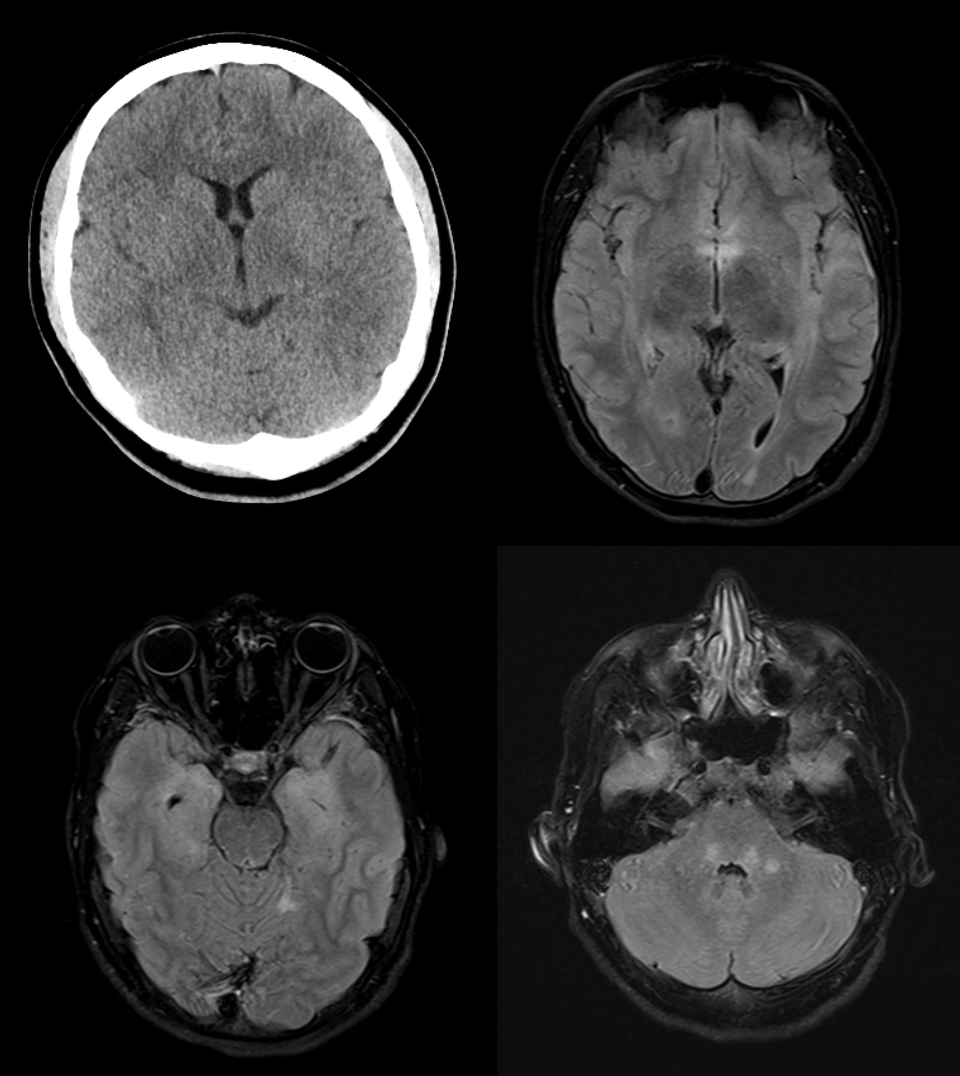

La TC eseguita in urgenza è stata utilizzata per escludere una patologia acuta come un'emorragia o un infarto. Successivamente è stata eseguita una risonanza magnetica (figura 1).

La risonanza magnetica ha mostrato una marcata iperintensità T2 nel midollo allungato, meno nel tegmento pontino, nel midollo cerebellare destro, nel midollo sottocorticale del corno posteriore sinistro, nel midollo insulare/temporale destro, intorno alle corna temporali, nel cingolo posteriore destro e frontalmente su entrambi i lati. I risultati dell’esame sono compatibili con un'encefalite limbica.